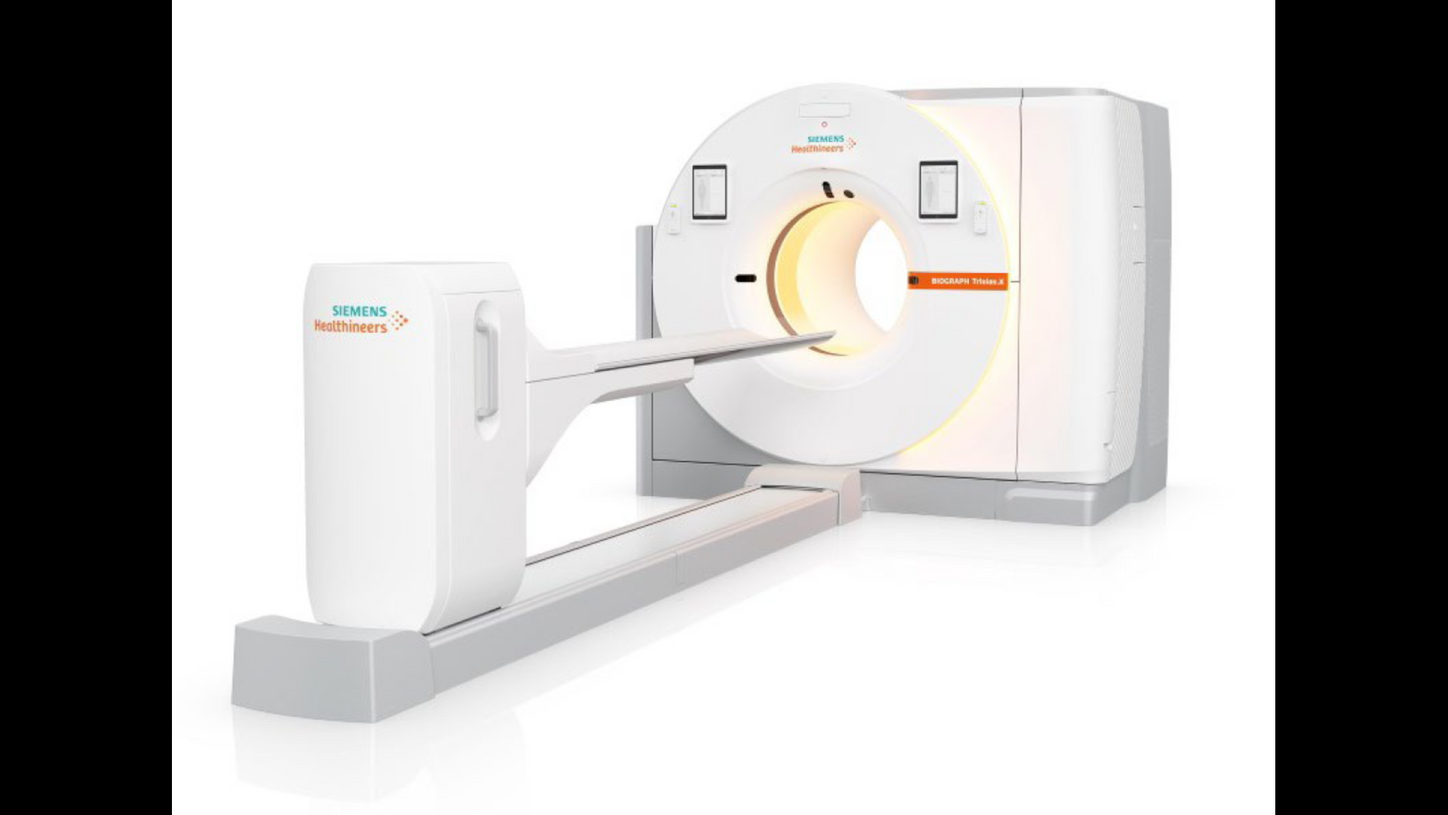

2025

Biograph Trinion.X meets evolving clinical demands with greater speed, sensitivity, and a patient-focused design. The system’s ultra-fast 197-picosecond time-of-flighta capability is a key advancement, along with an extended aFOV of up to 48 cm.